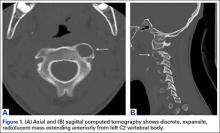

The patient presented with a computed tomography (CT) scan of his head and cervical spine and a magnetic resonance imaging (MRI) scan of the cervical spine. A magnetic resonance angiography (MRA) scan of the neck was ordered after his arrival.

Axial and sagittal CT (Figures 1A, 1B) showed a 1×1.2-cm discrete, expansile, lytic, radiolucent mass extending anterior from the left C2 vertebral body. The mass appeared to abut the left vertebral artery foramen. The cortical bone surrounding the lesion was thin but uniform. Sagittal and axial T1-weighted MRI (Figures 2A, 2B) showed the discrete, expansile, homogenous lesion with the same intensity as normal bone marrow. Sagittal and axial T2-weighted MRI (Figures 2C, 2D) showed a discrete, expansile, homogenous lesion with primarily high signal intensity. Sagittal short tau inversion recovery (STIR) MRI (Figure 2E) again showed the lesion with primarily low intensity. Given the close proximity of the lesion to the vertebral foramen, MRA was ordered; it showed the lesion was not interfering with the vertebral artery (Figure 2F).